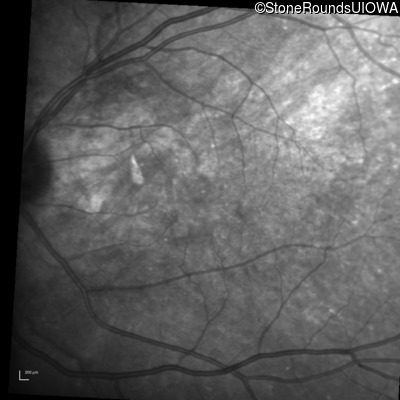

Infrared Fundus Photograph - Left - 20/25 +3

Exemplar